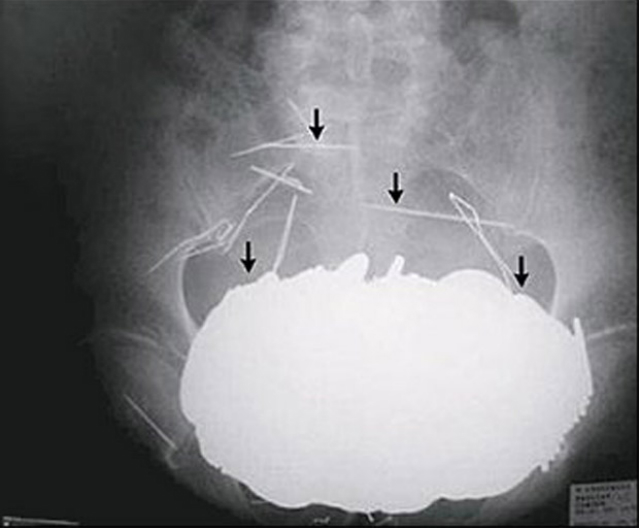

Incluso la policía le mandó sacar una radiografía para ver la sortija y acá está: